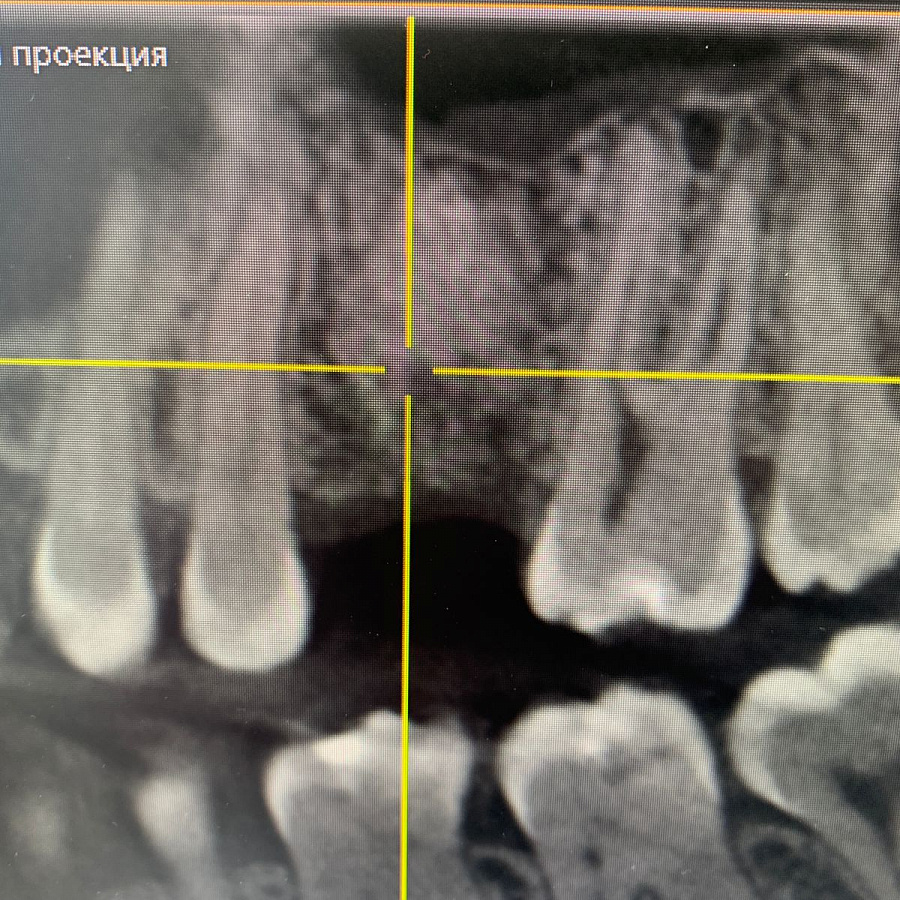

Через 6 месяцев после подсадки кости - контрольный снимок и установка зубного имплантата.